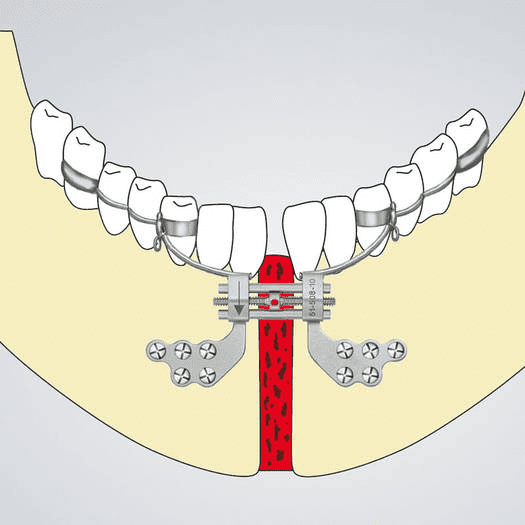

This is MSDO:

MSDO expands the lower jaw (particularly chin). The lower jaw can follow only so much the forced expansion the maxilla is subjected to from the MSE. This, in combination with the MSE can widen the chin, expand the palate, increase the lateral protrusion of the zygos

Now for the sake of thread, let's imagine that you were about to expand 20mm (extreme case), usually your safe bet is to expand 5-10mm, but when MSE is done simultaneously with MSDO, there wouldn't be much to rish about, other than bite correction.

You should done MSDO together with MSE, because if you're spliting the bone and expanding it, then you're literally changing the angulation of your tempomandibular joint. You're probably gonna need a little orthodontic movement of the molars to get them to match perfectly if you're doing MSE with MSDO, because MSDO expands the front teeth more than the back teeths.

⚠ The key is to do MSE and MSDO at the exact same time with the exact same amount of expansion, because than not only the chin would be expanded outward, also the rest of the mandible and thus the condiles can move in their natural place with the expansion of the maxilla...

This is MSDO:

MSDO expands the lower jaw (particularly chin). The lower jaw can follow only so much the forced expansion the maxilla is subjected to from the MSE. This, in combination with the MSE can widen the chin, expand the palate, increase the lateral protrusion of the zygos

It helped his midface, fwhr, and NCT a bit (wtf).Now for the sake of thread, let's imagine that you were about to expand 20mm (extreme case), usually your safe bet is to expand 5-10mm, but when MSE is done simultaneously with MSDO, there wouldn't be much to rish about, other than bite correction.

You should done MSDO together with MSE, because if you're spliting the bone and expanding it, then you're literally changing the angulation of your tempomandibular joint. You're probably gonna need a little orthodontic movement of the molars to get them to match perfectly if you're doing MSE with MSDO, because MSDO expands the front teeth more than the back teeths.

⚠ The key is to do MSE and MSDO at the exact same time with the exact same amount of expansion, because than not only the chin would be expanded outward, also the rest of the mandible and thus the condiles can move in their natural place with the expansion of the maxilla...